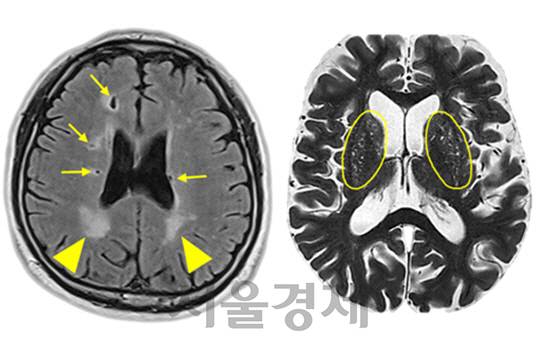

7일 서울대병원이 운영하는 서울시보라매병원에 따르면 남기웅·권형민 신경과 교수와 박진호 서울대병원 가정의학과 교수팀은 서울대병원 건강검진센터를 찾은 1,578명의 뇌 자기공명영상(MRI) 및 혈액 검사 결과를 분석해 호모시스테인의 혈청 농도와 뇌 소혈관질환 간의 연관성을 세계 처음으로 규명했다.

연구팀은 호모시스테인이 뇌 소혈관질환 위험을 높이는 주요 원인이며 다양한 뇌 소혈관질환들이 호모시스테인이라는 공통된 원인을 가지고 있음도 밝혀냈다.

호모시스테인은 음식물이 체내에서 소화될 때 만들어지는 아미노산으로 체내에 과다 축적되면 심혈관질환 및 뇌 조직 손상에 의한 치매 발병 위험을 크게 높이는 것으로 알려져 있다.